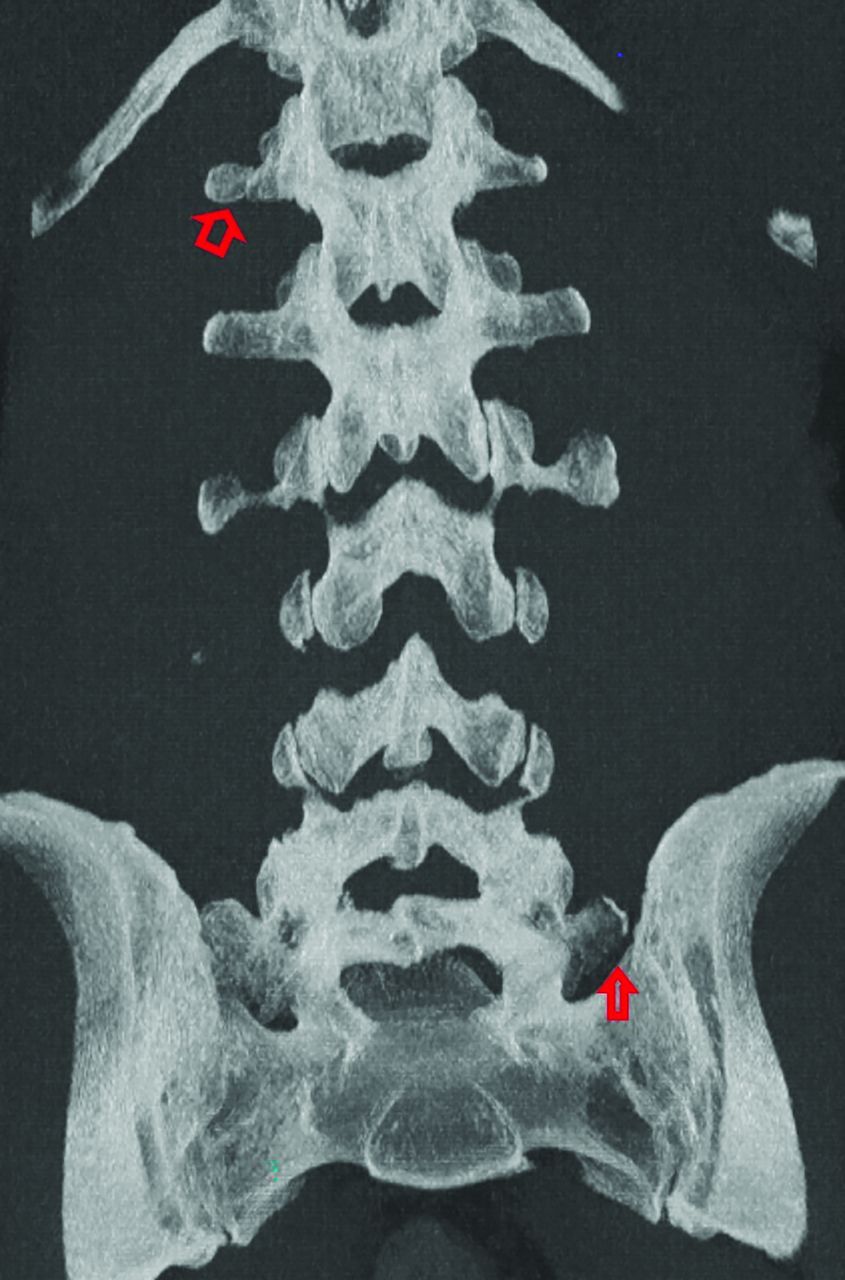

An example of both a thoracolumbar and lumbosacral transitional anatomy is given in Fig 7.

Example of thoracolumbar and lumbosacral transitional anatomy. Coronal MIP CT image of the lumbar spine demonstrates thoracolumbar and lumbosacral anatomy with an accessory ossification center on the right at T12 (open arrow) as well as a partially sacralized L5 vertebral body with an unfused left transverse process (closed arrow).